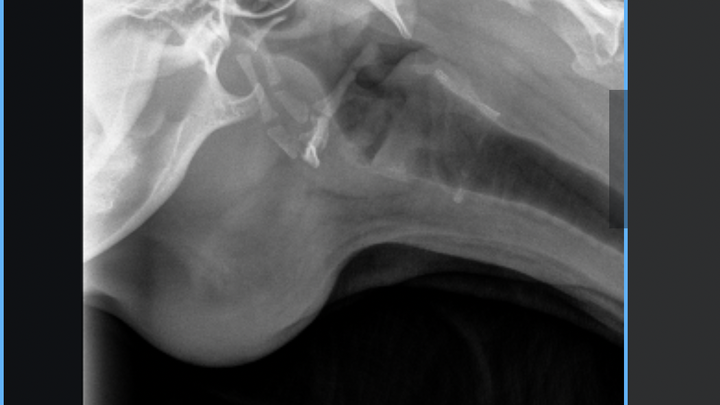

From the very beginning, Luna’s care team has worked tirelessly. She was sedated so her mouth could be explored, and started on antibiotics and pain medication. When the infection returned after her first round of treatment, her vet prescribed another course. As the abscess grew larger and harder, Luna underwent a fine needle aspiration and more advanced antibiotics. For a few days, it seemed like she was improving, but the infection came back stronger. At her latest appointment, Luna had x-rays and an ultrasound to rule out anything lodged in her throat. Thankfully, no foreign objects were found, but her vet felt surgery was too risky due to the size and location of the infection. That’s when we were referred to specialists, and now Luna must be seen as an emergency patient to get the care she needs.